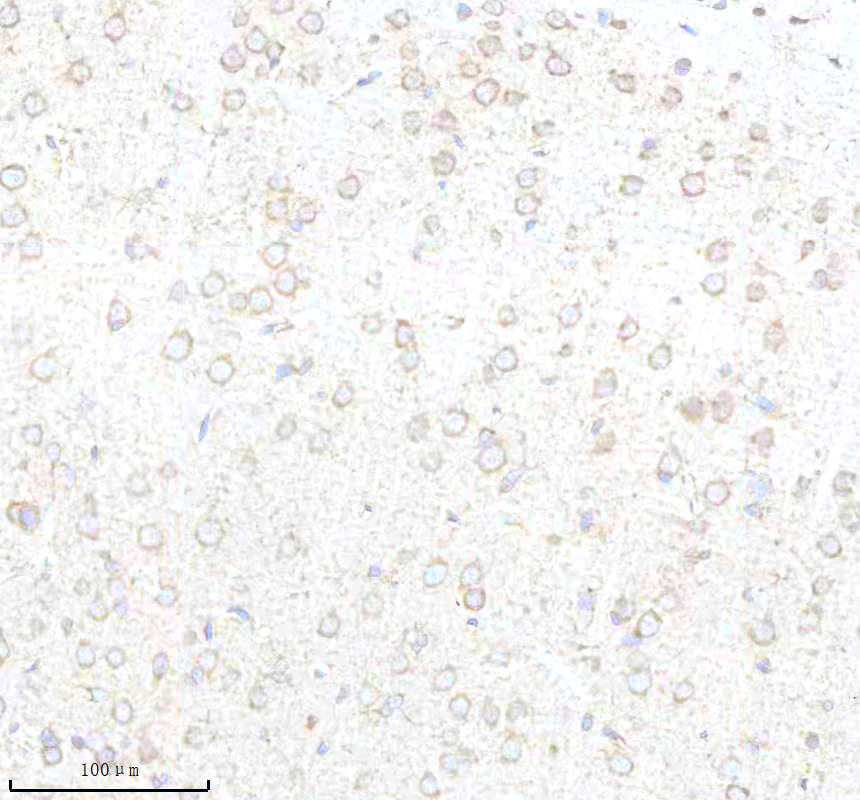

IHC analysis of BNIP3L using anti-BNIP3L antibody (BM5174) .

BNIP3L was detected in a paraffin-embedded section of mouse brain tissue. The tissue section was incubated with rabbit anti-BNIP3L Antibody (BM5174) at a dilution of 1:200 and developed using HRP Conjugated Rabbit IgG Super Vision Assay Kit (Catalog # SV0002) with DAB (Catalog # AR1027) as the chromogen.

IHC analysis of BNIP3L using anti-BNIP3L antibody (BM5174) .

BNIP3L was detected in a paraffin-embedded section of mouse brain tissue. The tissue section was incubated with rabbit anti-BNIP3L Antibody (BM5174) at a dilution of 1:200 and developed using HRP Conjugated Rabbit IgG Super Vision Assay Kit (Catalog # SV0002) with DAB (Catalog # AR1027) as the chromogen.